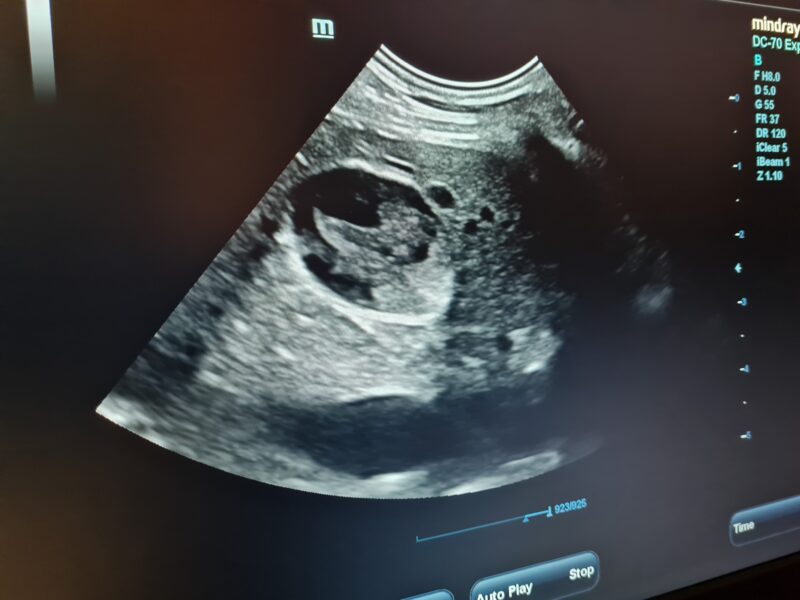

Mukoseele voidaan diagnosoida ultraäänitutkimuksella. Mukoseeleen viittava löydös on eriasteinen, hyperkaikuinen liikkumaton sakka sappirakossa. Verinäytteissä todetaan usein kohonneet maksa-arvot, ei kuitenkaan aina.